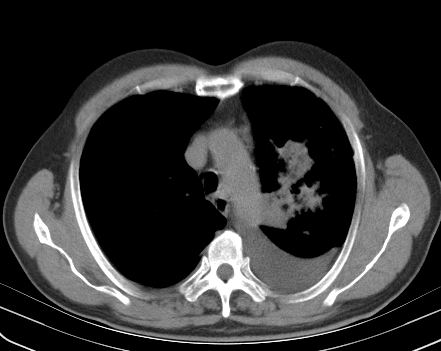

以下是引用老爱克斯新网客在2008-7-31 6:30:00的发言:[br]左肺上叶大片状病灶,左肺上叶支气管狭窄呈鼠尾状,左肺门增大,纵隔内见肿大淋巴结,左侧胸腔积液,余肺清晰。左肺中心型肺癌淋巴结转移,

以下是引用zjb在2008-7-31 6:32:00的发言:[br]左侧中心性肺癌 阻塞性肺炎 肺不张 胸腔积液 建议气管镜

以下是引用zjzjr在2008-7-31 8:45:00的发言:[br]考虑左侧中心性肺癌伴阻塞性肺炎,左肺上叶肺不张,纵隔淋巴结转移;左侧胸腔积液。建议行纤支镜检查。

以下是引用sdzyy在2008-7-31 8:47:00的发言:[br]病灶较治疗前有所进展,胸水增多, 左侧中心性肺癌 并 阻塞性肺炎 肺不张 胸腔积液 可能性大; 建议气管镜检查。 [br] [br]